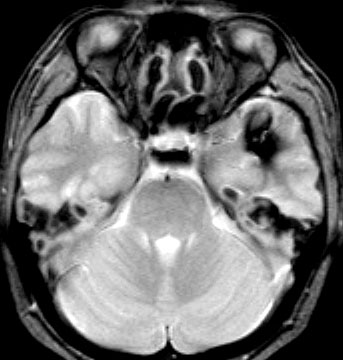

2度の延髄内出血を生じた海綿状血管腫です。でも初回の出血からすでに27年間がたちます。症状も回復して麻痺もなくていまは社会生活に困ることはありません。脳幹部の海綿状血管腫の中には1ヶ月に何回もひどい出血を繰り返すのもあるのですが,この例のように30年近い間に軽い出血が2回だけというのもあります。残念ながら正確にこれを予測することはできません。この患者さんの海綿状血管腫は手術で摘出すれば麻痺などの合併症の可能性があるのでしません。

脳幹部の海綿状血管腫を手術した方がいいかどうかはすごく慎重に判断しないといけないのです。場合によってはとても重い後遺症が手術ででてしまうこともあります。もちろん手術ですごく症状がよくなってとても元気に暮らしている患者さんもたくさんいますが,そうでない患者さんもいるのです。手術を決意する前に,少なくとももう一人の脳外科医からセカンドオピニオンを聞きましょう。